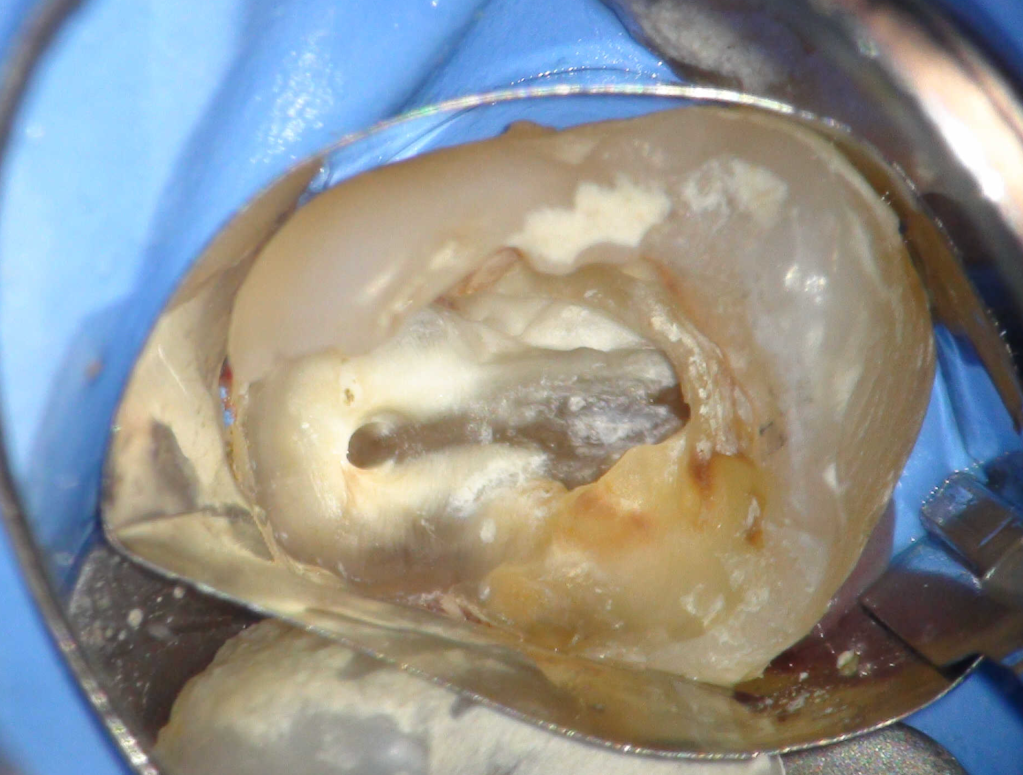

Reco preendo + 4 conductos molar superior